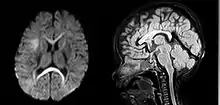

An MRI of a patient with benign familial macrocephaly (male with head circumference > 60 cm)

Macrocephaly is a condition in which circumference of the human head is abnormally large.[1] It may be pathological or harmless, and can be a familial genetic characteristic. People diagnosed with macrocephaly will receive further medical tests to determine whether the syndrome is accompanied by particular disorders. Those with benign or familial macrocephaly are considered to have megalencephaly.